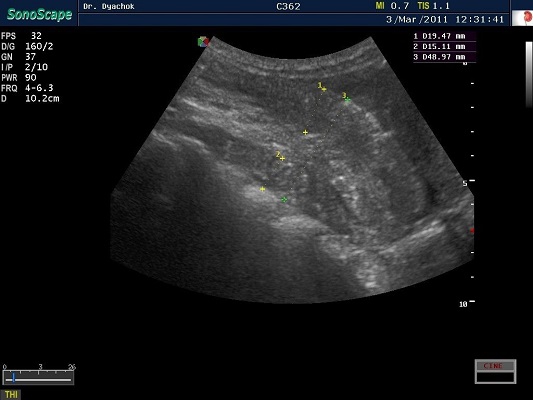

SonoScape S2N Vet – уникальная узи-система, выполненная в виде портативного ноутбука для легкой переноски. Отличается эта система цветным форматом визуализации, а также крайне чувствительными доплеровскими режимами, работающими на уровне премиальных аппаратов. При оптимальной цене – это очень хорошее и сбалансированное решение для ветеринарной клиники.

Диагональ монитора составляет 15,6 дюймов, что обеспечит комфортную работу для врачей и полный спектр визуализации для пациентов. Компактный вес не превышает 5 кг. (вместе с батареей), что оценят выездные бригады скорой помощи или ветеринары, выезжающие на дом.

Цифровая рабочая станция S2N Vet предполагает наличие жесткого диска для записи данных, составление и экспорт отчетов с возможностью добавления изображений, ведение базы данных пациентов.

Данный аппарат является незаменимым помощником в диагностической медицине. Ему нет конкурентов по оснащению, компактности и цене, а значит пора сделать правильный выбор для вашей клиники.